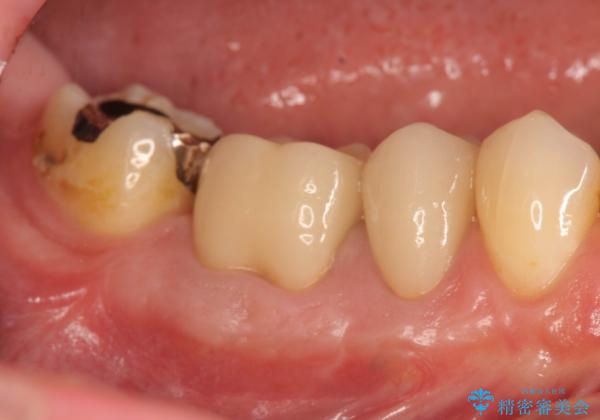

- 食事のたびに、銀歯の間や周囲に食ベカスが挟まったり溜まったりすることの改善を求めて来院されました。

銀歯の形状に問題があり、食べかすの詰まりやすい状況を、精度の高いセラミッククラウンに置き替えることで不快症状の改善を計画します。